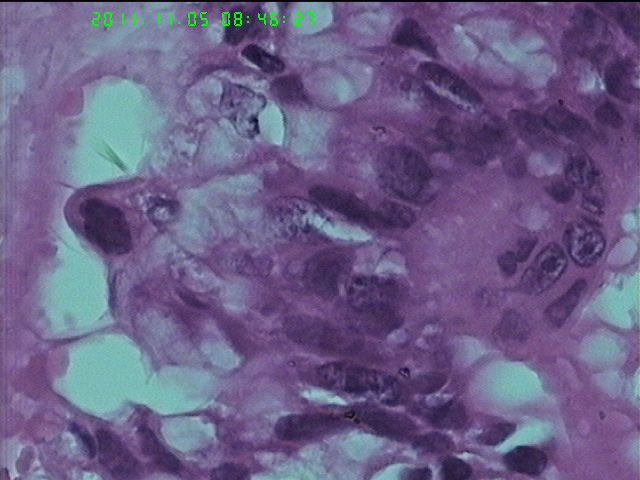

37岁女性患者,左卵巢肿块术中快速:恶性。术后左卵巢囊实性肿块14*9*5CM,灰黄色,部分乳头状,粘液样外观;子宫内膜厚1.5CM;网膜见多个小结节。图1--14左卵巢  15-19网膜  20--23宫腔

图1、4、5、6、11中可见疏松组织,网状结构,并见可疑透明小体,加上患者年纪较年轻,卵黄囊瘤不能除外,粘液腺结构可能是卵黄囊中的内胚层成分。且形态上与网膜结节相似。